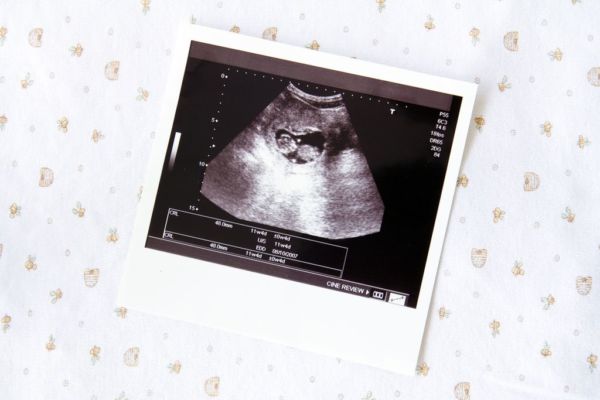

Η πρώτη φορά που «βλέπετε» το μωρό σας είναι ανάμεσα σε ασπρόμαυρες σκιές. Όμως, το υπερηχογράφημα δεν σας χαρίζει μόνο την πρώτη φωτογραφία του. Βοηθάει το γιατρό να βεβαιώνεται ότι όλα πάνε καλά. Τι είναι ο προγεννητικός υπέρηχος;

Πρόκειται για μια εξέταση που πραγματοποιείται με ειδικό μηχάνημα (υπερηχοτομογράφος), το οποίο χρησιμοποιώντας τα ηχητικά κύματα αναπαράγει εικόνες του εμβρύου και των εσωτερικών οργάνων του, του πλακούντα και του αμνιακού σάκου. Έτσι, ο γιατρός μπορεί να βεβαιωθεί ότι το μωρό αναπτύσσεται σωστά και να κάνει μετρήσεις ώστε να υπολογίσει το ύψος και το βάρος του. Η διαδικασία με την οποία πραγματοποιείται η εξέταση είναι απλή και εντελώς ανώδυνη: Ο γιατρός, αφού απλώσει στην κοιλιά σας ένα τζελ, ώστε να εφάπτεται σωστά η κεφαλή του μηχανήματος (ηχοβολέας) με το δέρμα, κινεί τον ηχοβολέα ελέγχοντας στην οθόνη και αποθηκεύοντας τις εικόνες. Κατά μέσο όρο, μία εξέταση με υπέρηχο διαρκεί περίπου 15-20 λεπτά. Κάθε πότε πρέπει να κάνω υπέρηχο;

- Εφόσον η εγκυμοσύνη σας εξελίσσεται ομαλά και δεν έχουν παρουσιαστεί προβλήματα, ο πρώτος αναλυτικός υπέρηχος γίνεται συνήθως μεταξύ της 6ης και της 11ης εβδομάδας. Σε αυτόν ερευνάται ο αριθμός των εμβρύων, η θέση τους, η ηλικία της κύησης και εκτιμάται η βιωσιμότητά τους. Σε πολλές περιπτώσεις, το υπερηχογράφημα αυτό γίνεται με κολπικό υπέρηχο που σε αυτή τη φάση της εγκυμοσύνης δίνει καλύτερες εικόνες.

- Το δεύτερο γίνεται μεταξύ 11ης και 14ης εβδομάδας και απεικονίζει τη θέση του πλακούντα, την ανάπτυξη των οργάνων του εμβρύου, ενώ ανιχνεύονται τυχόν ανωμαλίες. Επιπλέον, γίνεται μια ειδική μέτρηση που ονομάζεται «αυχενική διαφάνεια» και υπολογίζει την πυκνότητα της περιοχής του πίσω μέρους του λαιμού του μωρού. Ο υπέρηχος αυτός συνδυάζεται με εξέταση αίματος, που εκτιμά την πιθανότητα ύπαρξης γενετικών ανωμαλιών, όπως το Σύνδρομο Down (PAPP-A test). Κατά τη διενέργεια της αυχενικής διαφάνειας, μπορούμε να δούμε το φύλο του εμβρύου (με πιθανότητες περίπουν 75%).